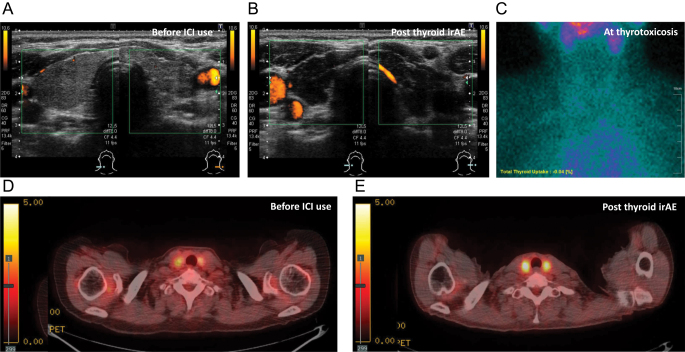

Immune checkpoint inhibitors (ICIs) frequently cause immune-related adverse events (irAEs), with thyroid irAEs being the most common endocrine-related irAEs. The incidence of overt thyroid irAEs was in the range of 8.9-22.2% in real-world settings, typically triggered by antibodies against PD-1 and PD-L1 and rarely by anti-CTLA-4 antibodies alone. The representative clinical course involves biphasic changes in thyroid function: transient thyrotoxicosis and subsequent persistent hypothyroidism. The identified risk factors for thyroid irAEs include the presence of thyroid autoantibodies, thyroid uptake on 18F-FDG-PET, prior use of tyrosine kinase inhibitors (TKIs), high BMI and high thyroid-stimulating hormone levels. There is evidence that overt thyroid irAEs are associated with good prognosis, at least in non-small cell lung cancer. Although the clinical features have been well clarified, the management strategies require further refinement. Routine monitoring of thyroid function every 4-6 weeks during ICI therapy is recommended for early detection of thyroid irAEs. While thyrotoxicosis generally requires observation only, hypothyroidism should be promptly treated with levothyroxine replacement. Continuation of ICI therapy is typically feasible in patients with thyroid irAEs, provided their overall health remains stable. However, these strategies were largely based on clinical experience with monotherapy. As combination ICI therapies have been developed as first-line treatments, antitumor agents may modify the clinical features of thyroid irAEs. For example, cytotoxic agents can delay the onset of thyroid irAEs, while TKIs are often linked to early-onset hypothyroidism, independent of ICI use. Given the increasing diversity and complexity of cancer immunotherapy, it is essential to vigilantly screen for thyroid irAEs.